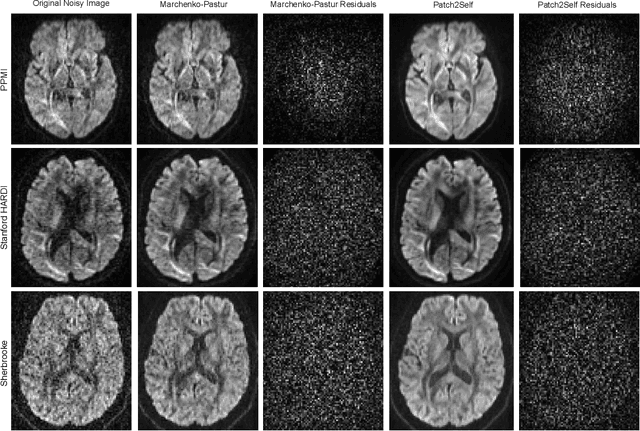

Abstract:Diffusion-weighted magnetic resonance imaging (DWI) is the only noninvasive method for quantifying microstructure and reconstructing white-matter pathways in the living human brain. Fluctuations from multiple sources create significant additive noise in DWI data which must be suppressed before subsequent microstructure analysis. We introduce a self-supervised learning method for denoising DWI data, Patch2Self, which uses the entire volume to learn a full-rank locally linear denoiser for that volume. By taking advantage of the oversampled q-space of DWI data, Patch2Self can separate structure from noise without requiring an explicit model for either. We demonstrate the effectiveness of Patch2Self via quantitative and qualitative improvements in microstructure modeling, tracking (via fiber bundle coherency) and model estimation relative to other unsupervised methods on real and simulated data.